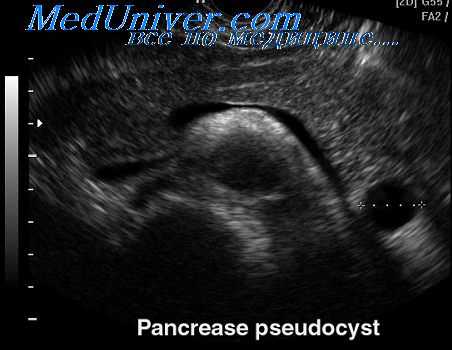

У пациентов с подозрением на псевдокисту поджелудочной железы:

• Тонкоигольная аспирация содержимого кисты (бактериологическое исследование, определение уровня амилазы, цитологическое исследование).